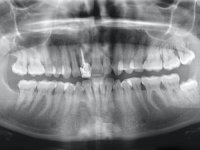

Female patient, 41 years old, non-smoker. It presented tooth 11 with a composite resin restoration, of great extension, very infiltrated and aesthetically poor. In the imaging exam, it was verified that the endodontic treatment was not technically satisfactory, but asymptomatic for almost 20 years. Between teeth 11 and 12 it showed a periodontal pocket certainly related to the non-adapted restoration. Tooth 11 showed a reduced mesiodistal diameter in relation to the symmetrical one. Medium thickness periodontal with satisfactory oral hygiene.